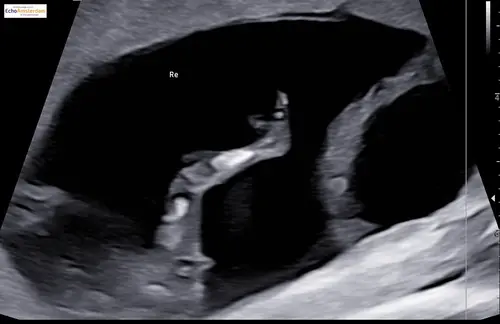

Ik vind het zo knap dat mensen hier wijs uit komen, ik kom er zelf maar niet uit, maar ben stiekem ook wel benieuwd of onze 2de een jongen of meisje is, kan iemand helpen? 😊

Alvast bedankt !

Duidelijk meisje!